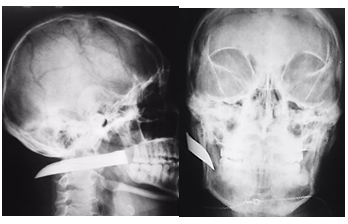

The patient was moved to the operating room to complete the remotion of knife blade under general anesthesia. Using the same wound as the point of approach, and with previous confirmation of no affection to vascular vital structures, the knife blade was retracted without major bleeding, the wound washed and closed with polyglycolic acid in deep planes and nylon in the skin, without incidents or accidents (Figures 3) (Figures 4).

Figure 3 Clinical photograph of the surgical field and the removed foreign body.